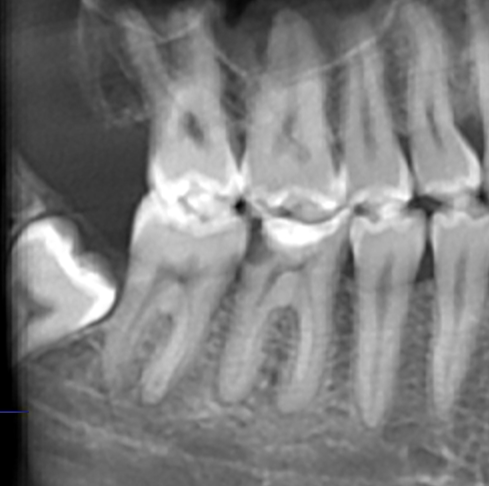

• Глубокое поражение пульпы кариесом без возможности её лечения терапевтическими методами;

• Прогрессирование периодонтита – воспаления зубного корня;

• Ослабление десны и связочного аппарата, удерживающего корни в лунке.

Удаление также показано в случаях, когда коренные зубы, особенно «восьмёрки» занимают неправильное положение и оказывают негативное влияние на зубной ряд. Необходимость в установке протезных систем иногда тоже требует экстракции, но только в случаях, когда установка системы осложнена.